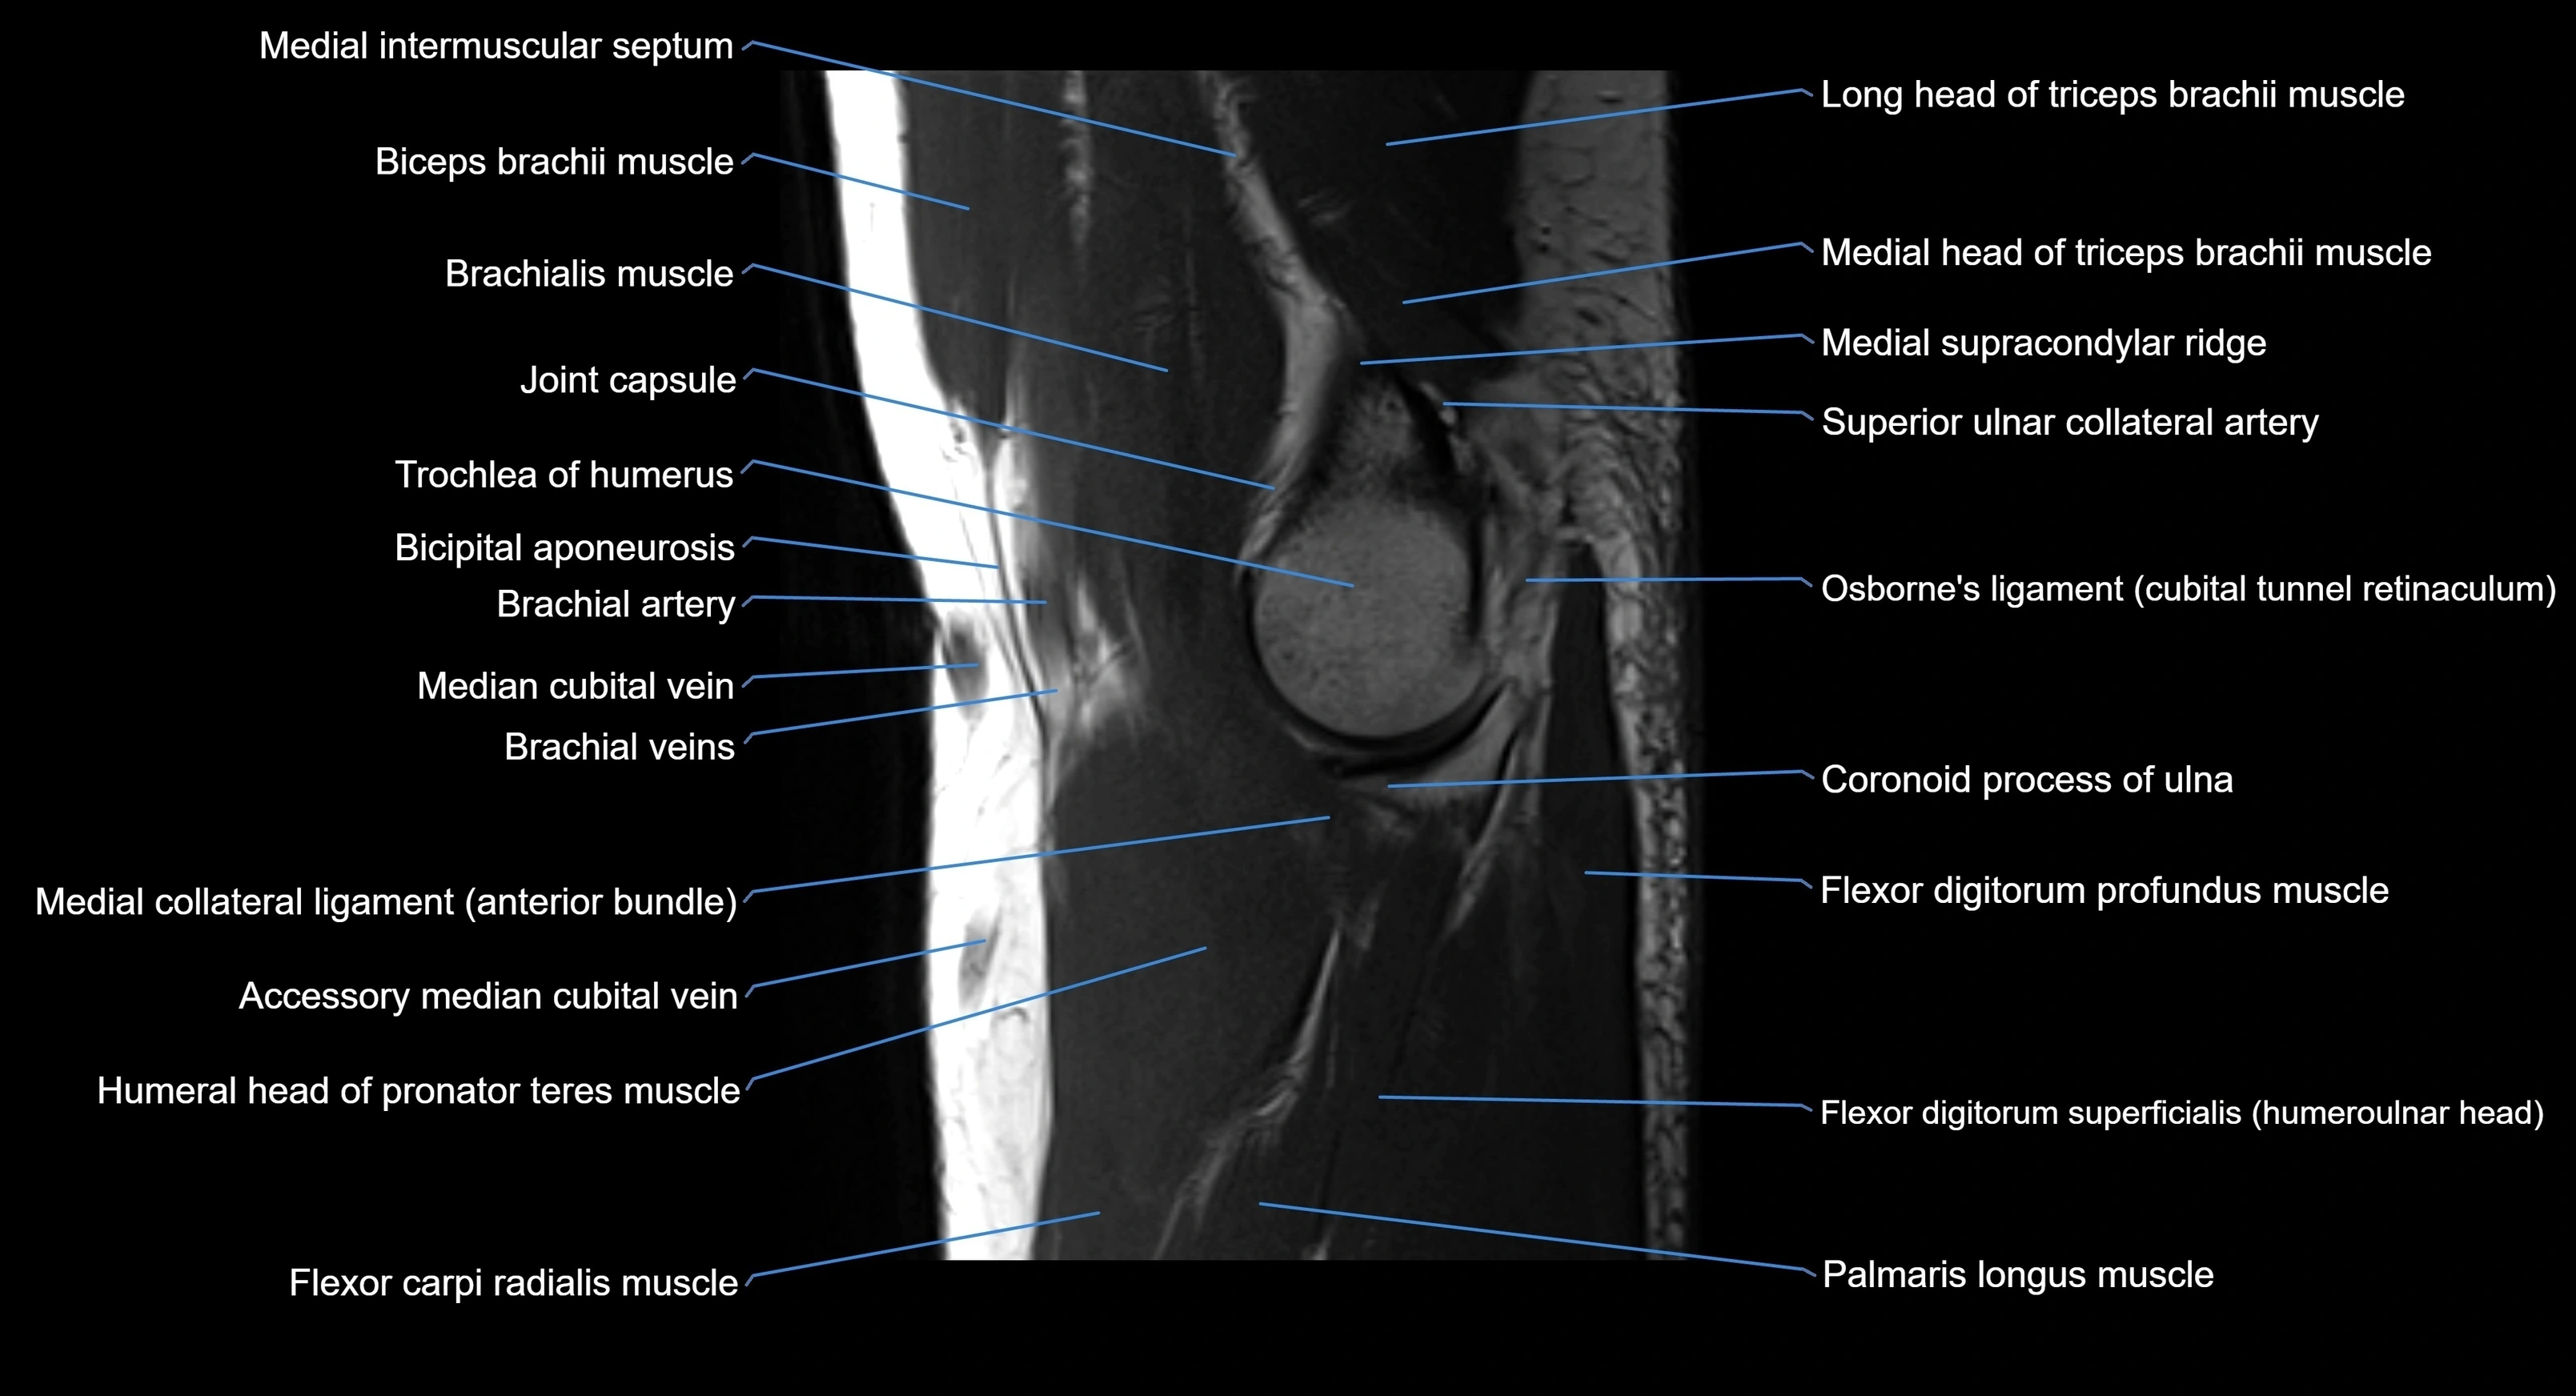

MRI image

image